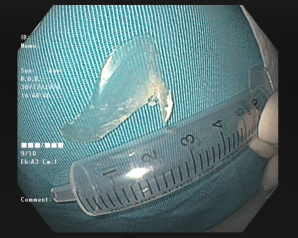

Thức ăn ứ đọng trên vị trí xương mắc và xương gà hình chạc 3 được gắp ra ngoài

Trường hợp khác là bệnh nhân nữ 35 tuổi, trú tại phường Giếng Đáy, thành phố Hạ Long. Bệnh nhân bị hóc xương cá từ tối trước ngày vào viện, sau hóc cảm giác nuốt vướng, nuốt đau vùng cổ. Ekip nội soi Khoa Nội tiêu hóa đã tìm thấy dị vật xương cá lớn hình chiếc rìu, dài 03 cm, nhiều góc cạnh sắc nhọn mắc tại thực quản vị trí cách cung răng trên 17cm, bề mặt niêm mạc thực quản trầy xước nông, không chảy máu. Xương cá sau đó được gắp ra ngoài an toàn.